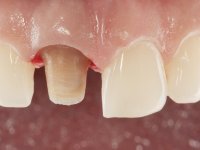

The patient came to the consultation because she did not like the “dark line next to the gums” that she had on her upper right central incisor.

Female patient, 33 years old, non-smoker. Tooth 11 with endodontic treatment rehabilitated with a crown. This crown shows an infiltrated cervical interface. The smile line was high, this area being very visible. The patient had a thick gingival phenotype and good oral hygiene.

A pre-print was performed to make a crown in dual-cured resin. After a cross-section with a turbine, the infiltrated crown was removed with a microluxador. The dental stump was re-prepared to better define the shape and location of the cervical margin. It was necessary to place composite resin on the buccal surface of the provisional crown to improve its esthetics. The impression was made using a double-mix technique with two-viscosity, quick-setting silicones. In the laboratory, a crown with a ceramic-coated Zr infrastructure was made. After placing it in the mouth, we verified that the crown showed a greater translucency than the symmetrical one, not fulfilling our aesthetic goals. The ceramist had the opportunity to observe the situation in the clinic, collecting records for later rectification. The new crown was placed in the mouth and approved by the patient. The final cementation was done with resin-reinforced glass ionomer cement.